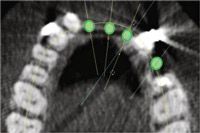

FIGS. 1-4 Clinical view of maxillary arch showing missing teeth (Fig. 1). Axial view showing planned implants in area 8, 9, 10, 12 (Fig. 2). Cross-sectional view showing buccal and lingual bone for implant placement (Fig. 3). Periapical view showing spacing of implants post placement (Fig. 4).

One of the most important parameters in planning for ideal esthetics in the anterior region is to space the implants accordingly. The literature suggests a minimum of 3 mm between implants and 2 mm between an implant and a natural tooth. Through analysis of a CBCT, the correct spacing can be planned. The axial view from a CBCT shows spacing of implants (Fig. 2).